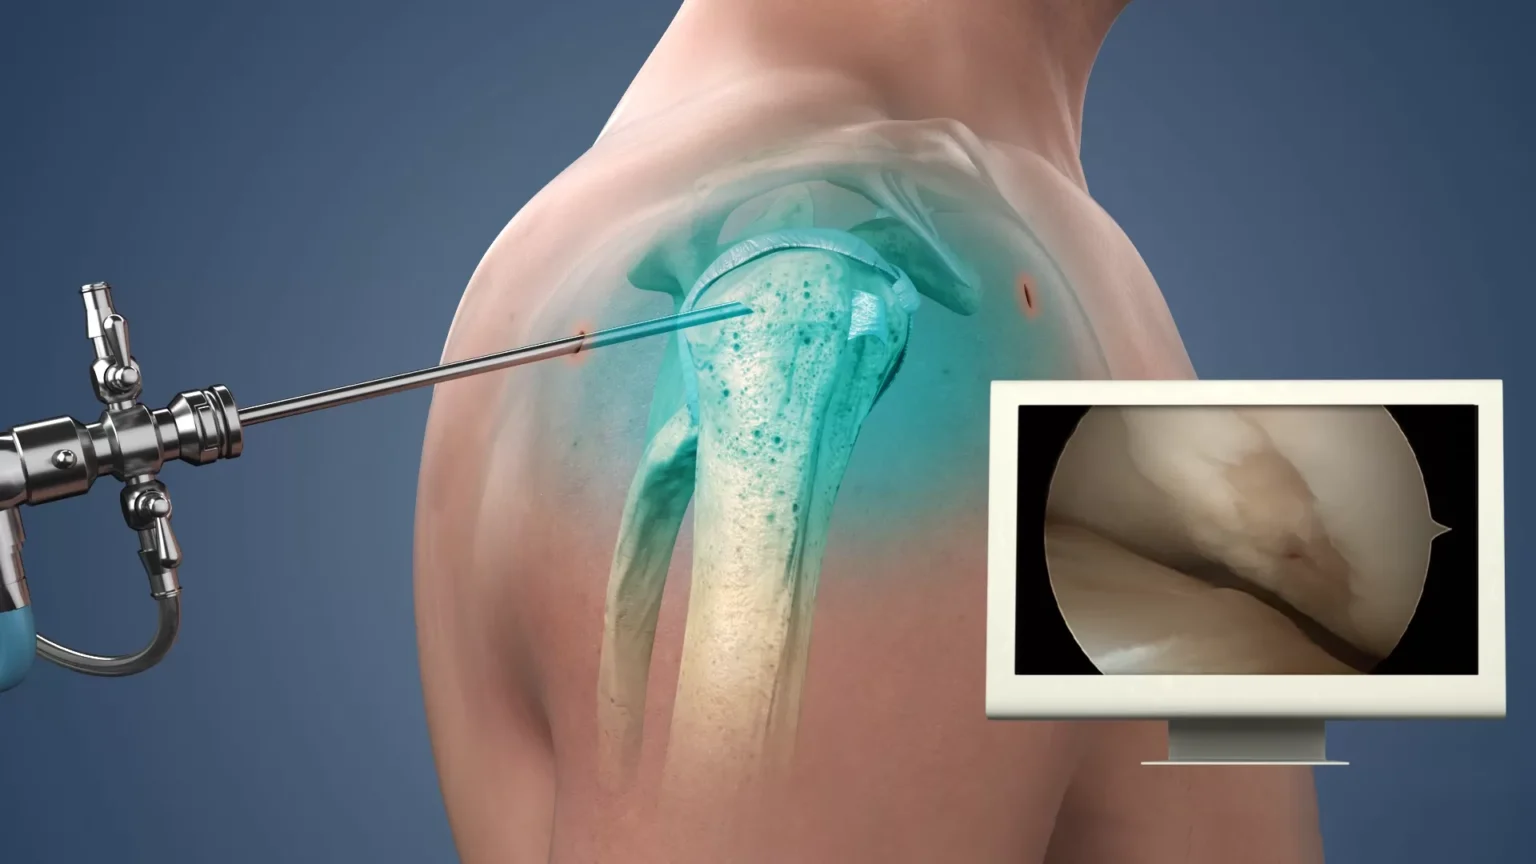

La Artroscopia permite tratar lesiones articulares mediante pequeñas incisiones, reduciendo el tiempo de recuperación y las complicaciones. Este procedimiento se aplica principalmente en rodillas, hombros y otras articulaciones, con resultados efectivos y seguros.